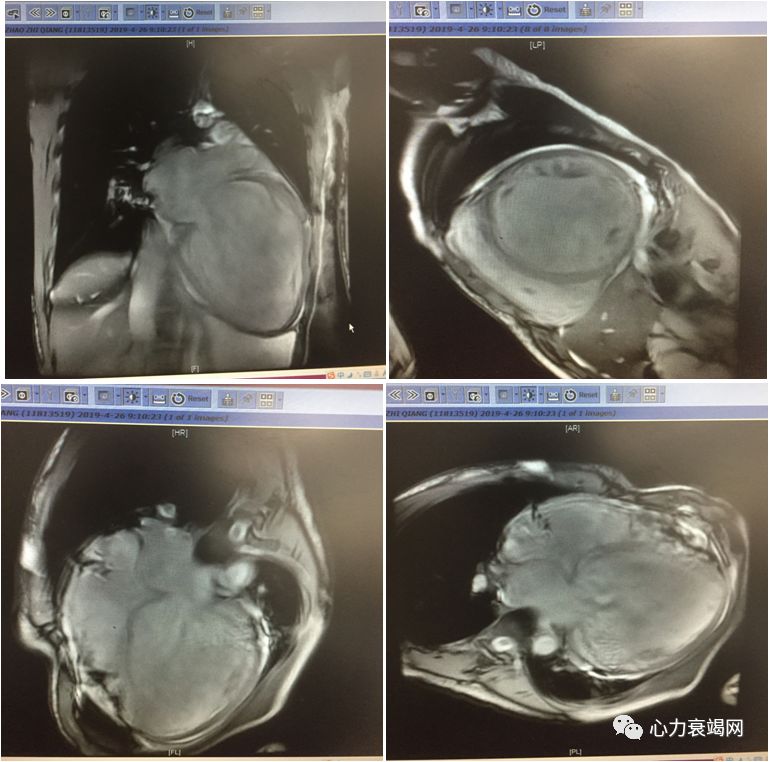

磁共振

主动脉瓣功能性二瓣化畸形并中重度关闭不全,左室高度扩大并收缩功能明显减退,考虑瓣膜性心肌病可能性大。